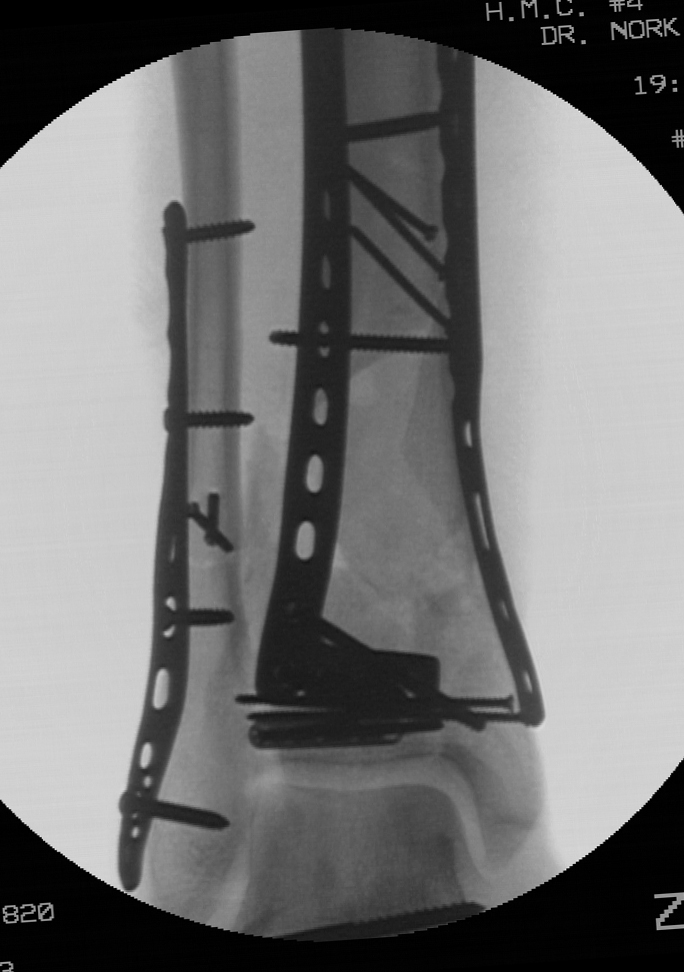

The entire articular block was then reduced relative to the tibial shaft and an anterolateral plate was placed in a submuscular fashion beneath the anterior compartment musculature through the anterolateral incision. In order prevent varus, a medial plate was slid along the subcutaneous anteromedial face of the distal tibia through a one centimeter incision over the medial malleolus Finally, antibiotic beads were placed into the osseus defect.

Initially, unrestricted range of motion exercises of the ankle joint and subtalar joint was encouraged two weeks following the definitive articular reconstruction, despite the presence of the large osseus defect. The implants were felt to be of sufficient strength and the patient was compliant. The patient was allowed to begin weight bearing at 12 weeks from his definitive articular reduction, which was 6 weeks following his bone grafting procedure. Weight bearing was initially restricted to a walking boot for 6 weeks given the presence of the grafted defect, followed by unrestricted weight bearing with regular shoe wear. Radiographs at 6 months from his articular reconstruction demonstrate maintenace of alignment and the presence of the bone graft.

Radiographs at one year show incorporation of the bone graft. The patient was full weight bearing without restrictions. Ankle range of motion was 15 degrees dorsiflexion and 30 degrees plantar flexion. The patient had some persistent discomfort and stiffness.